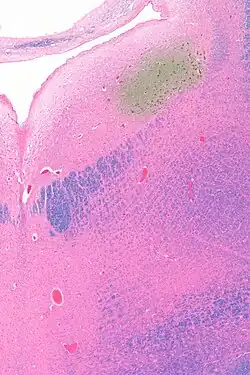

The locus coeruleus (LC) is located in the posterior area of the rostral pons in the lateral floor of the fourth ventricle. It is composed of mostly medium-size neurons. Melanin granules inside the neurons contribute to its blue colour. Thus, it is also known as the blue nucleus, or the nucleus pigmentosus pontis (heavily pigmented pontine nucleus).[5] The neuromelanin is formed by the polymerization of norepinephrine and is analogous to the black dopamine-based neuromelanin in the substantia nigra.